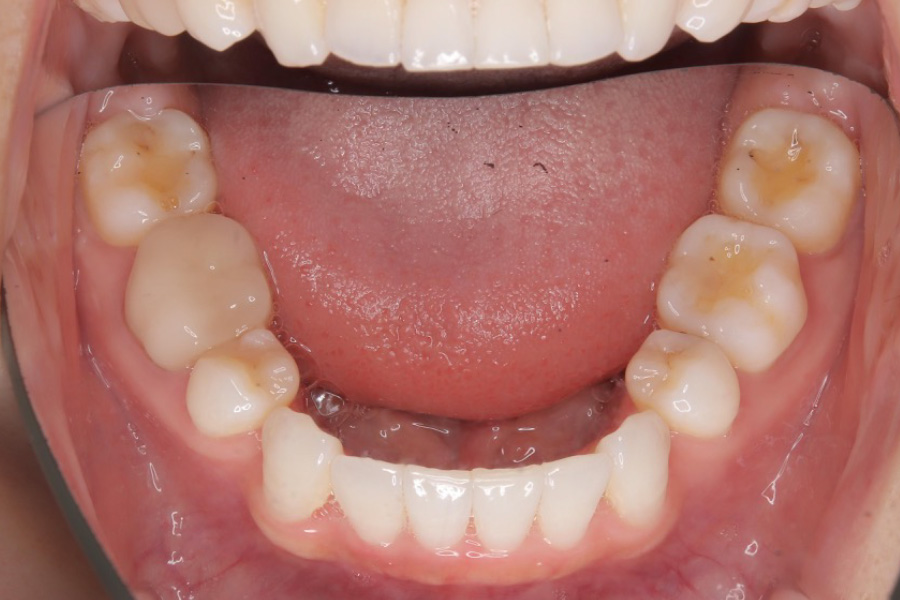

【20代女性】

八重歯、下の歯のガタつきを

インビザライン矯正で治療したケース

治療前

主訴 八重歯、下の歯のガタつきが気になる

治療内容 インビザライン矯正

小臼歯抜歯